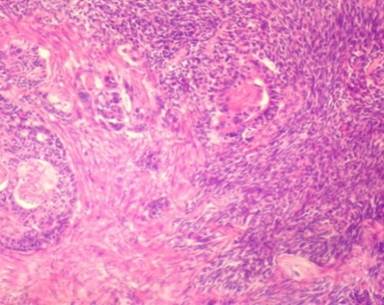

Microscopically, the tumour yielded two components. The first component was a relatively well-differentiated adenocarcinoma, while the second component showed poorly-differentiated solid tissue of mesenchymal origin (Figure 3). Immunohistochemically, the epithelial component was strongly reactive for antibodies to CK7 and CD34, while the sarcomatoid component was negative for all CK antibodies but strongly reactive for the antibody to vimentin (Figure 4). The postoperative period was uneventful. The patient was discharged the ninth postoperative day. A venous port implanted six weeks after the operation and he received eight cycles of gemcitabine. Despite the poor prognosis, the patient is still alive and without evidence of the disease 16 months after the operation.

Figure 3. Histological examination revealed duct-like and spindle-shaped atypical cells (left) and carcinosarcoma appearance (right) after hematoxylin and eosin stain (magnification x45). |